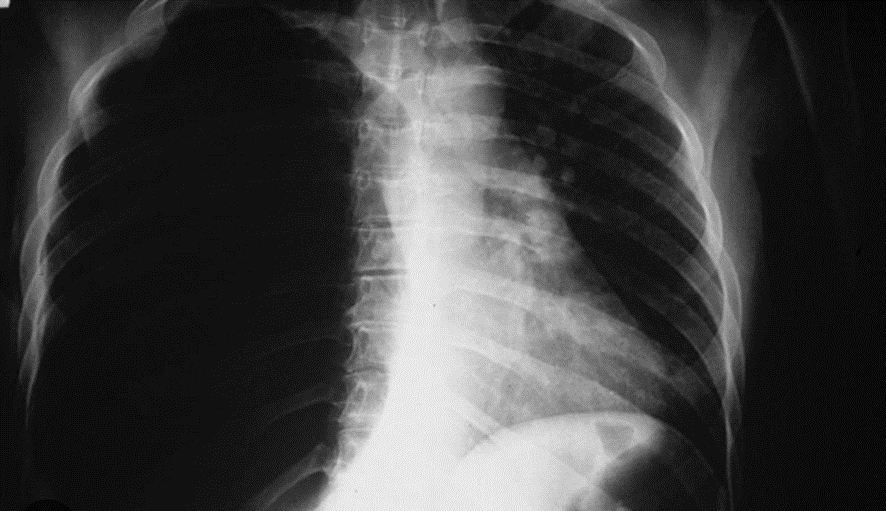

NEUMOTORAX